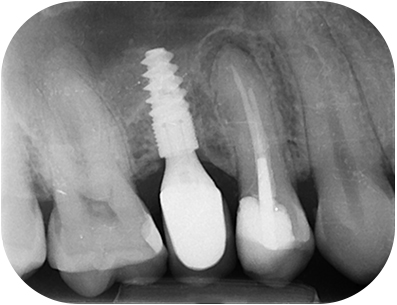

prémolaire, la corticale sous-sinusienne est intacte.Fig. 03 : Ia corticale sous-sinusienne

est intacte.

L’infection observée sur la racine palatine pourrait être liée à une obturation courte(2) ou à la persistance d’un biofilm intra-canalaire(3).

En l’absence de LIPOE sur la racine vestibulaire, le pronostic reste très favorable(4). Mais nous avons pu accéder à cet apex sans trop forcer, lors de la préparation.

radio per-opératoire cone ajustéFig. 07 : radio per-opératoire cone ajusté.

Radio per-opératoire après WVCFig. 08 : radio per-opératoire après WVC.